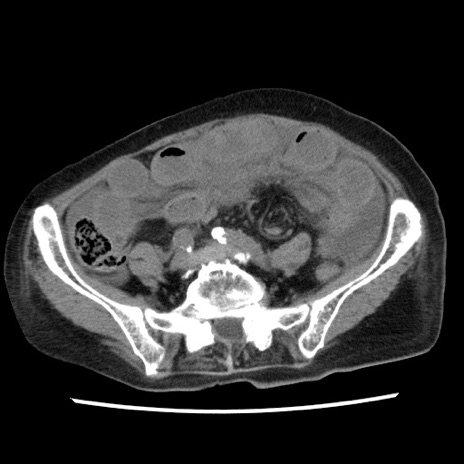

症例1(横断像)

【症例】80歳代女性

【主訴】腹痛

【現病歴】8時間前から腹痛あり来院。

【既往歴】糖尿病、脂質異常症、子宮体癌にて子宮全摘術

【身体所見】意識清明・会話良好だが腹痛で苦悶様、全腹部にわたって反跳痛と圧痛あり

【データ】WBC 13600、CRP 0.14、LDH 224、CK 90